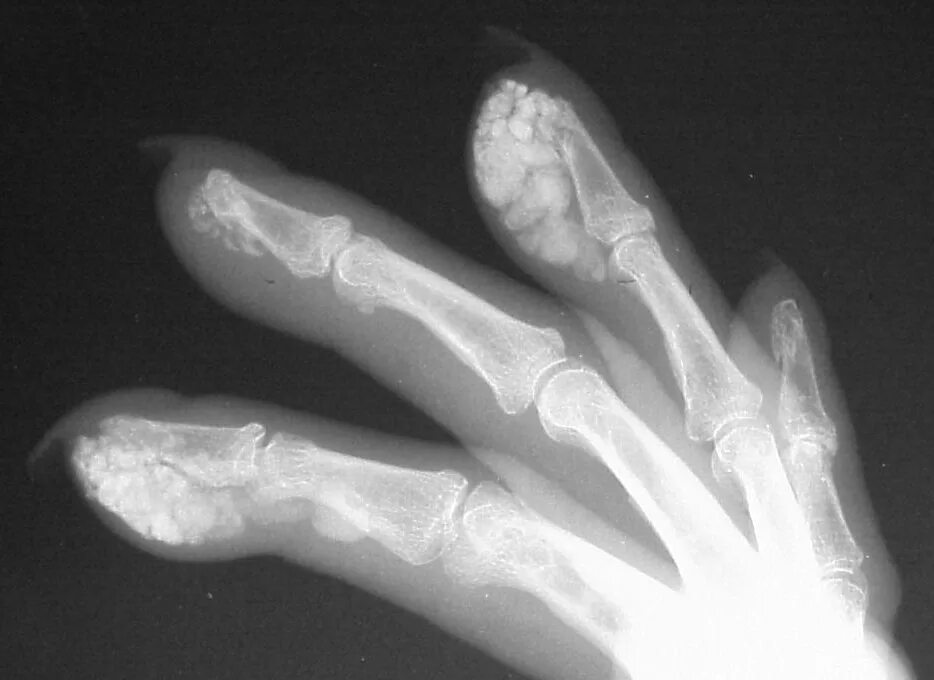

Отложение кальция